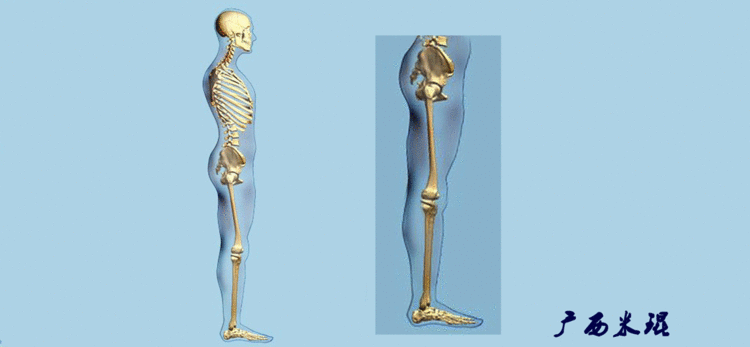

机械轴要分前后位及侧位,站立前后位(也就是冠状面)股骨头中心与踝关节中心的连线通过膝关节中心,这是下肢的机械轴线,也就是下肢力线,常说Mikulicz线。冠状面的力线评估在临床工作中最常用、最基础、最重要。

站立侧位(矢状面)股骨头中心与踝关节中心的连线也通过膝关节中心,这也是下肢的机械轴线,这也是下肢力线。

矢状面的下肢力线常常被医生忽视,其实它的改变也是膝关节疼痛的常见原因。